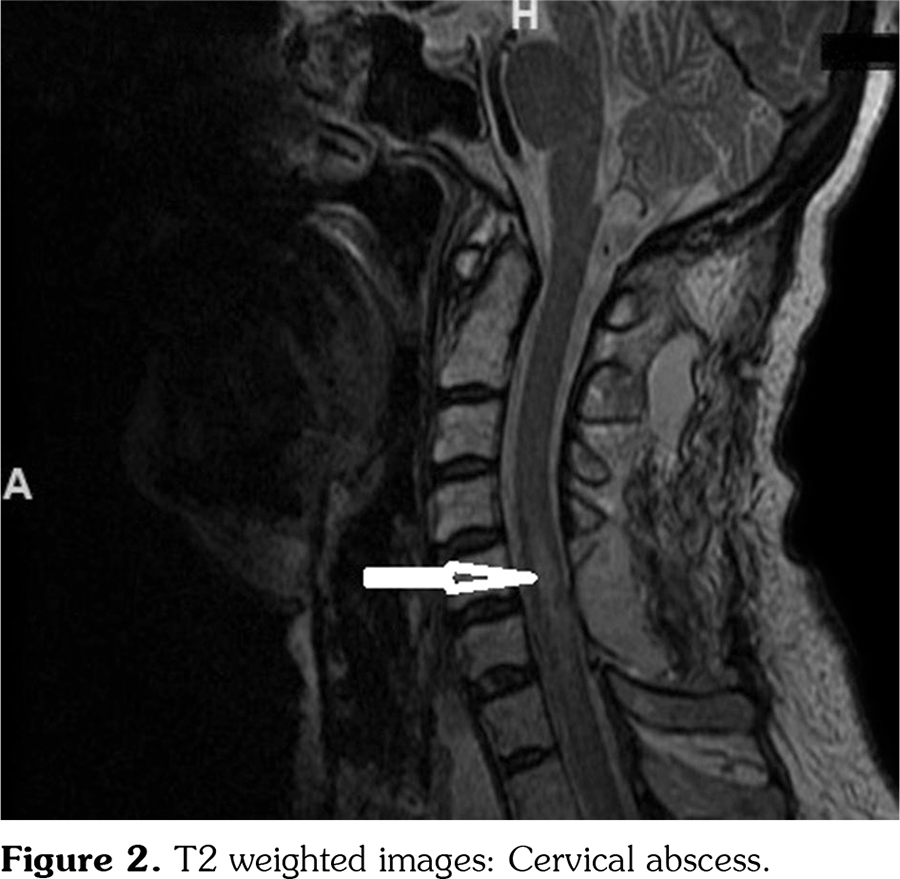

A 56-year-old female patient with RA for the last 18 years had received methotrexate, methylprednisolone, leflunomide, etanercept, infliximab, and adalimumab in the past but all the drugs were discontinued due to inadequate response. TCZ therapy was started with an 8 mg/kg/month infusion. She had also been using warfarin sodium due to grade 2 aortic insufficiency and mitral valve prosthesis for five years. The patient did not use any other drugs. After the 20th day of the fourth trial of TCZ infusion, the patient was admitted to the emergency department with sudden back pain, weakness, and numbness in her legs, bladder and bowel dysfunction. There was no history of trauma. Her blood pressure was 130/90 mmHg. Neurological examination showed the presence of complete paraplegia. Laboratory findings were as follows: hemoglobin: 12.2 g/dL (normal), platelet: 193•109/L (normal), white blood count: 6•109/L (normal), aspartate aminotransferase: 55 U/L (high), alanine aminotransferase: 50 U/L (high), blood urea nitrogen: 16 mg/dL (normal), creatinine: 1.1 mg/dL (normal), INR: 2.1 (normal), C-reactive protein (CRP): 1.2 mg/L (normal). Peripheral blood smear was normal. Factor 13 and fibrinogen levels were normal too. Urgent magnetic resonance imaging (MRI) of the thoracolumbar spine demonstrated an elongated space-occupying mass with convexity to the spinal canal at the level of T8-T12 vertebra which was seen as a hyperintense mass on the T2 weighted images and hypointense on the T1 weighted images (Figure 1). It was observed via immediate exploratory surgery that there was blood in the epidural space and decompressive laminectomy was performed. A written informed consent was obtained from the relatives of patient.